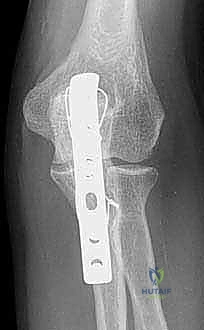

Image

FIG 1 • The Mayo classification of olecranon fractures accounts for the factors that will influence treatment decisions: displacement, comminution, and dislocation or subluxation of the articulations.